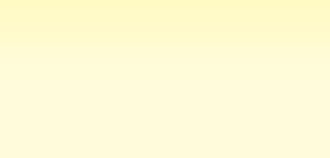

Ursache vieler Krankheiten und Schmerzen!

Ursache vieler Krankheiten und Schmerzen!